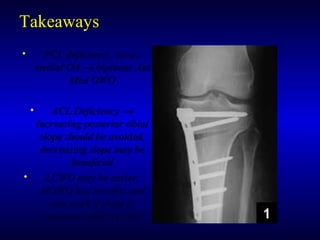

TakeawaysTakeaways

• PCL deficiency, varus,PCL deficiency, varus,

medial OAmedial OA →→ biplanar Antbiplanar Ant

Med OWOMed OWO

• ACL DeficiencyACL Deficiency →→

Increasing posterior tibialIncreasing posterior tibial

slope should be avoided,slope should be avoided,

decreasing slope may bedecreasing slope may be

beneficialbeneficial

• LCWO may be easier,LCWO may be easier,

MOWO has benefits andMOWO has benefits and

can work if slope iscan work if slope is

maintained/decreasedmaintained/decreased